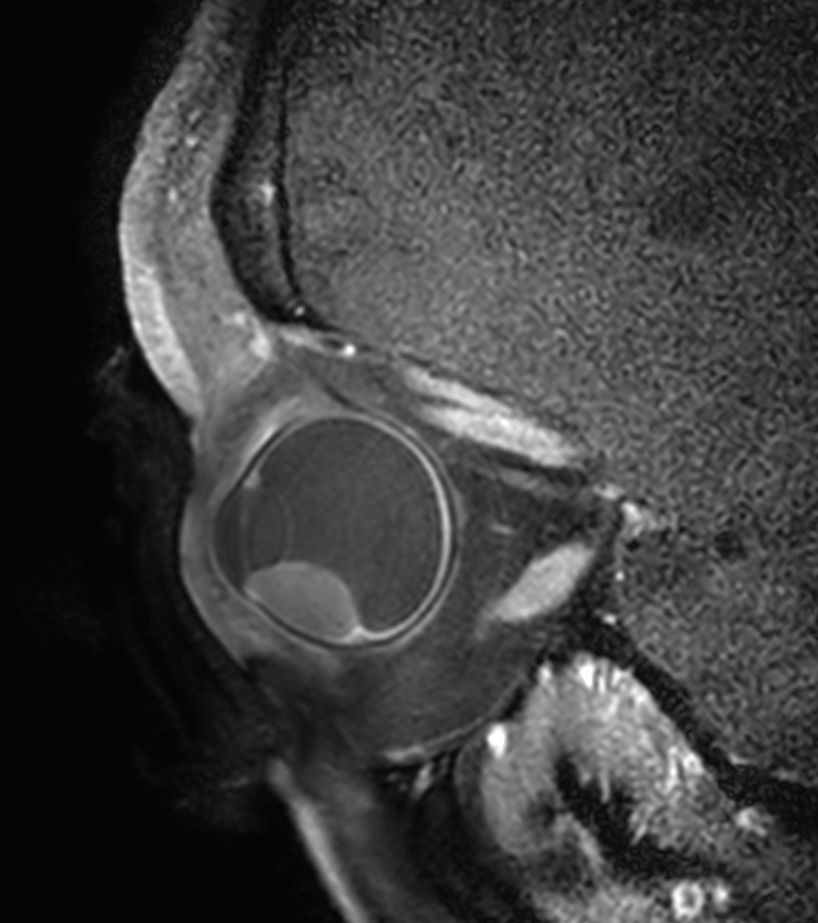

4 different 3D isotropic sequences, T1W with and without fat saturation, T2W and T1W fat saturation post-contrast are used to evaluate the tumor prior to treatment. Isotropic sequences are used to allow for good quality multiplanar reconstruction corresponding to the location of the tumor; as the tumor can be located anywhere in the eye, optimal visualization often requires an assessment of different oblique planes, which is facilitated by the 3D isotropic sequences. The pre-contrast sequences help evaluate the tumor size and location and the post-contrast sequence provides additional information such as identifying tumor that has seeped through the sclera behind the eye and differentiating tumor vs associated retinal detachment.

Higher in-plane resolution 2D sequences are used to better evaluate the tumor and screen for infiltration to the adjacent structures, which can have direct therapeutic consequences.